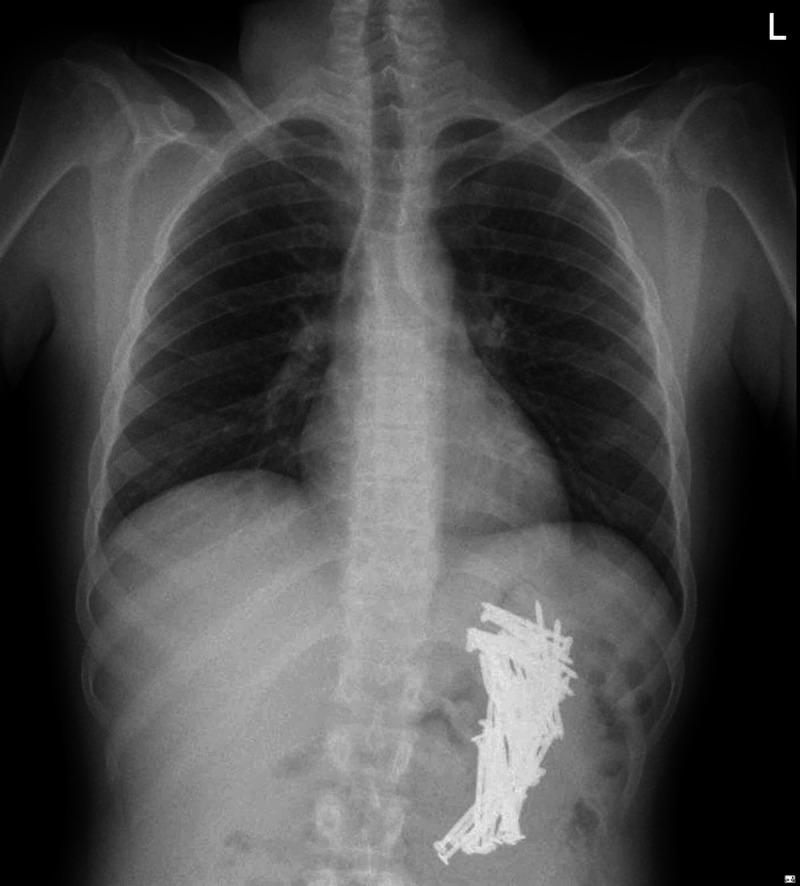

Ingestion of foreign bodies is common within the pediatric population; in adults, it occurs more commonly in those with a psychiatric background. Diagnosis of such cases can be readily made based on plain abdominal X-rays. As reported, many foreign bodies pass through the gastrointestinal tract without complications, obstruction, bleeding, and perforation. The ultimate decision of the best management approach for such cases should be made based on the available expertise as well as the patient's specific factors. Observation, endoscopic removal, and surgical intervention are all acceptable approaches in cases of metal foreign body ingestion. We report a case of a 29-year-old male patient brought to the emergency department following ingestion of multiple sharp nails. He underwent surgical exploration, which resulted in the retrieval of 73 metallic nails.

吞食异物在儿科人群中很常见;在成人中,吞食异物在有精神病史的人群中更为常见。此类病例的诊断可根据腹部平片轻松做出。据报道,许多异物可通过胃肠道而不出现并发症、梗阻、出血和穿孔。对于此类病例,最佳治疗方法的最终决定应基于现有的专业知识以及患者的具体因素。在金属异物吞食病例中,观察、内镜取出和手术干预都是可接受的方法。我们报告一例29岁男性患者,因吞食多根尖锐钉子被送往急诊科。他接受了手术探查,结果取出了73根金属钉子。